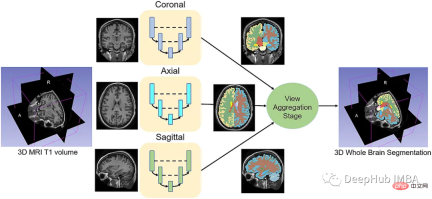

给定一组MRI脑扫描I = {I1,…In}及其对应的分割S = {S1,…Sn},我们想要学习一个函数fseg: I -> S。我们将这个函数表示为F-CNN模型,称为QuickNAT:

QuickNAT由三个二维f - cnn组成,分别在coronal, axial, sagittal视图上操作,然后通过聚合步骤推断最终的分割结果,该分割结果由三个网络的概率图组合而成。每个F-CNN都有一个编码器/解码器架构,其中有4个编码器和4个解码器,并由瓶颈层分隔。最后一层是带有softmax的分类器块。该架构还包括每个编码器/解码器块内的残差链接。

现在可以训练模型了。对于QuickNAT需要在3个(coronal, axial, sagittal)2d切片上训练3个模型。然后再聚合步骤中组合三个模型的概率生成最终结果,但是本文中只演示在coronal视图的2D切片上训练一个F-CNN模型,因为其他两个与之类似。